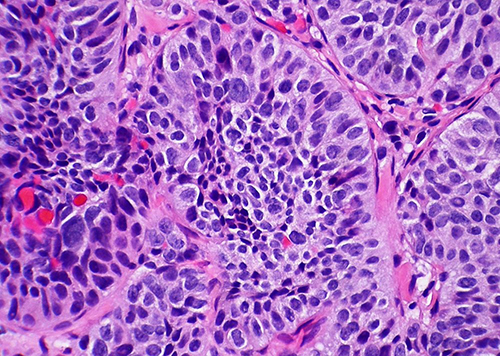

Генерация циркулирующих опухолевых клеток (ЦКО), ключевой этап метастазирования опухоли, происходит во время хирургической резекции опухоли, часто выполняемой под общим наркозом. Для него используется анестетик пропофол. Однако его влияние на ЦОК и метастазирование опухоли оставалось в значительной степени неизвестным.

Исследование проводилось на голых мышах, которым пересаживались опухолевые клетки и одновременно с этим вводилась низкая или стандартная доза пропофола. Используя несколько методов, ученые оценивали, как пропофол влияет на адгезию и распространение опухолевых клеток.

По результатам исследования было установлено, что пропофол приводил к образованию большего числа метастазов опухоли легких у мышей, по сравнению с контрольной группой, которой анестезия не вводилась. Пропофол усиливал адгезию и распространение опухолевых клеток. Однако ученые подчеркивают, что требуются дальнейшие исследования.